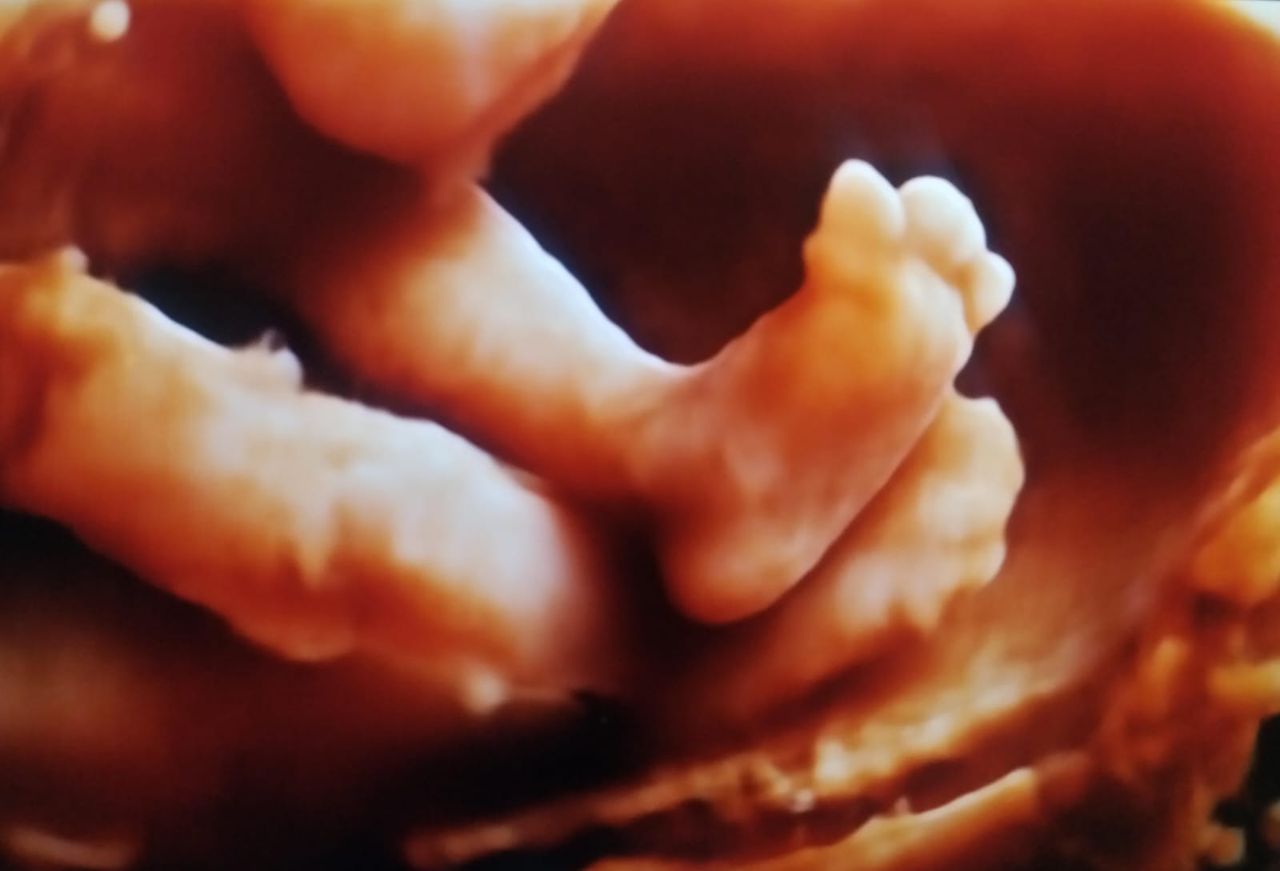

Realizamos ultrasonidos 3D y 4D obstétricos, donde puedes ver en tiempo real a tu bebe así como la evaluación Doppler para determinar el bienestar fetal.

• Ultrasonido 3D

$2,000

• Ultrasonido 4D